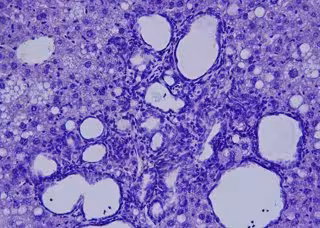

Archivo - Colangiocarcinoma visto al microscopio.

Archivo - Colangiocarcinoma visto al microscopio. - CNIC - Archivo